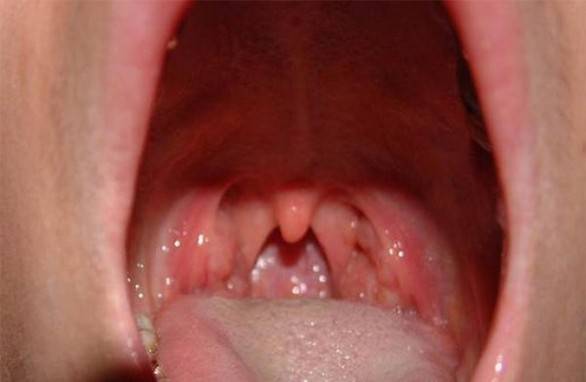

Шта је стрептокок - групе, симптоми, дијагноза, лечење и превенција антибиотицима

Стрептококна инфекција - патогени микроорганизми који изазивају појаву разних болести. Сазнајте више о симптому ...